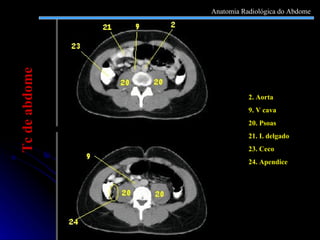

2. Aorta 9. V cava 20. Psoas  21. I. delgado 23. Ceco 24. Apendice Tc de abdome Anatomia Radiológica do Abdome

2. Aorta 9.V cava 20. Psoas 21. I. delgado 23. Ceco 24. Apendice Tc de abdome Anatomia Radiológica do Abdome